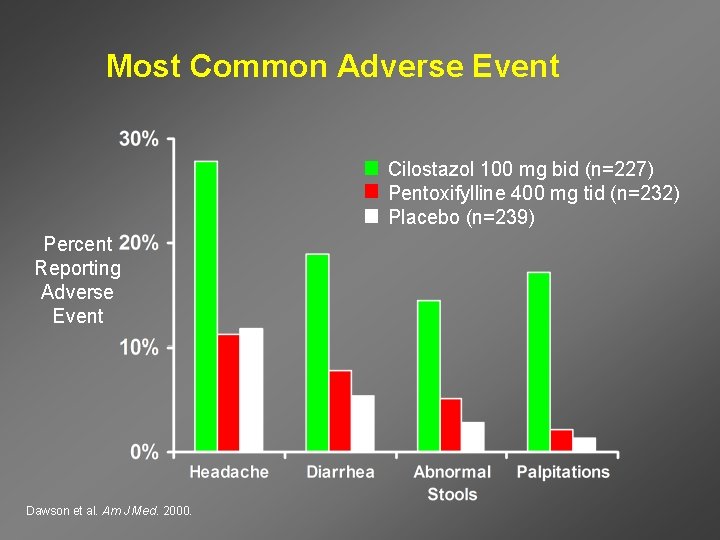

Most Common Adverse Event Cilostazol 100 mg bid (n=227) Pentoxifylline 400 mg tid (n=232) Placebo (n=239) Percent Reporting Adverse Event Dawson et al. Am J Med. 2000.